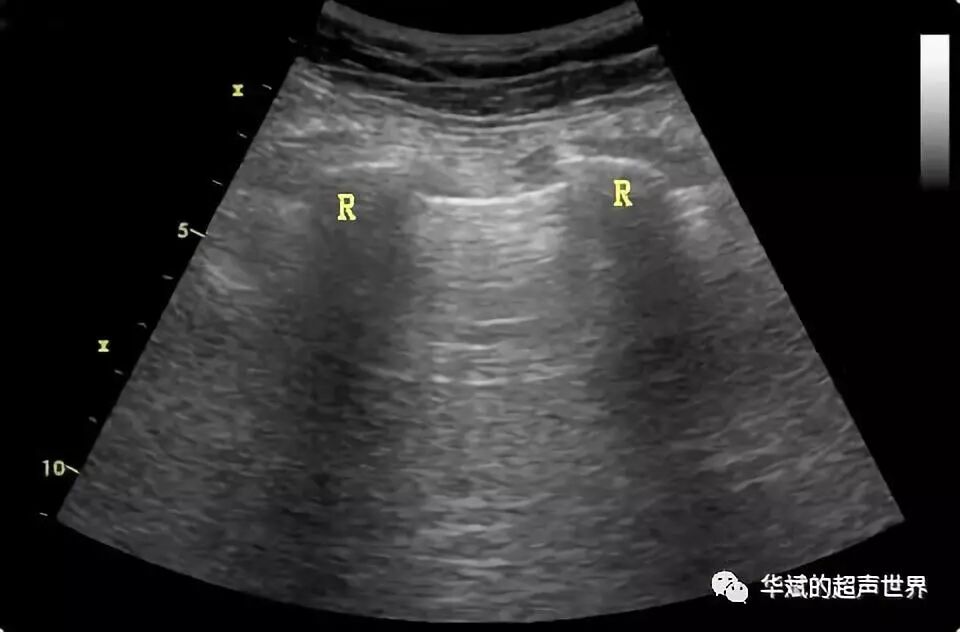

我们在胸部扫查时会发现,肋间的胸膜肺线在纵断时并非平直的,而是两端上翘的凹面,这也是由于声束通过肋骨边缘时发生折射形成的。(图3)

图3 肋间的胸膜线呈凹面,也是折射伪像。